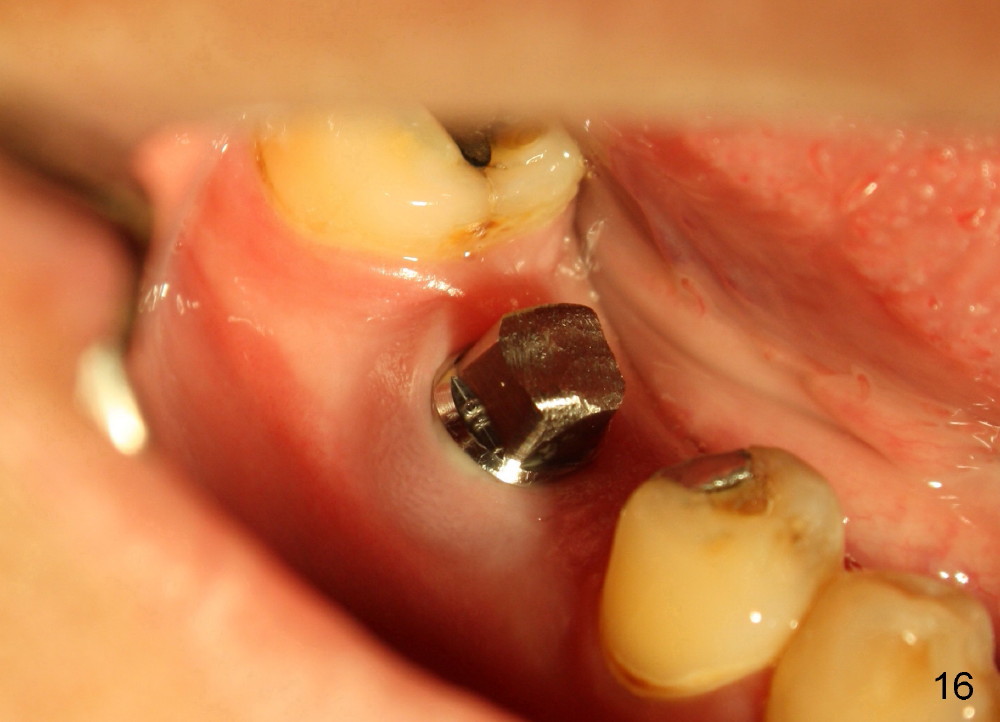

A 38-year-old lady agrees to have implant placement 7 years after loss of the crown of the lower right first molar (Fig.1,2). When the tooth is extracted, the septum is found to be low (Fig.3,4). To confirm it, a PA is taken (Fig.5). To initiate an osteotomy in the septum, it is trans-sectioned with thin osteotomes as shown in Fig.4 insert (black line). A 2 mm pilot drill is placed in the septum (Fig.6: P). The osteotomy is enlarged by 2.5-4.0 mm reamers (Fig.7,8), followed by insertion of 6x17 mm tapered tap at the depth 14 mm (Fig.9). The osteotomy is further enlarged by 4.5 and 5.0 mm reamers. A 6.0x14 mm one piece implant is placed initially. The trajectory is not ideal. A 6.0x14 mm one piece implant is placed initially. The trajectory is not ideal. The implant is removed from the osteotomy partially and reinserted with improved trajectory (Fig.11, compare to Fig.10 (red line)). Primary stability is high. There is not much bone mesiodistally so that the trajectory is easily changed in that direction. After abutment preparation, mixture of autogenous bone (harvested from reamers) and allograft is placed in the residual mesial and distal sockets (Fig.12). To contain the bone graft, an immediate provisional is placed (Fig.13 P). The occlusal plane of the provisional is significantly lower than that of the adjacent teeth to avoid micromovement of the implant. The patient is advised to eat soft food on the left side. Six days postop, the patient returns for prophy. The provisional is removed; the bone graft appears to be incorporating into the socket (Fig.14). After recementation, the provisional remains in place for 3.5 months; PA shows increased bone density in the mesial and distal sockets (Fig.15, compare to Fig.5,11). Due to insurance coverage, the patient defers fabrication of definitive restoration for at least 7 months. The immediate provisional is finally lost 8.5 months postop: the gingiva attaches to the 1-piece implant (Fig.16), while the density of the mesial socket increases (Fig.17 *) with formation of the cortex (lamina dura) coronally (v). Before the provisional (Fig.18 P) is removed for cementation of the definitive restoration, black shadow (*) is noted over the buccal gingiva. It is partially due to buccal placement (Fig.19) and partially due to buccal atrophy over a period of 10.5 months postop. How to prevent buccal placement? Positioning the first pilot drill in the septum buccolingually is a key. Eleven months post crown (Fig.20 C) cementation, the black shadow remains, but there is no tenderness. If the implant threads are immediately underneath the periosteum, there is tenderness.

The patient will return for immediate implant at #14. Do not forget placing an implant as palatal as possible. There is no sign of infection at #30 three years 9.5 months post cementation because of water pik for #3 endo failure (Fig.25,26).